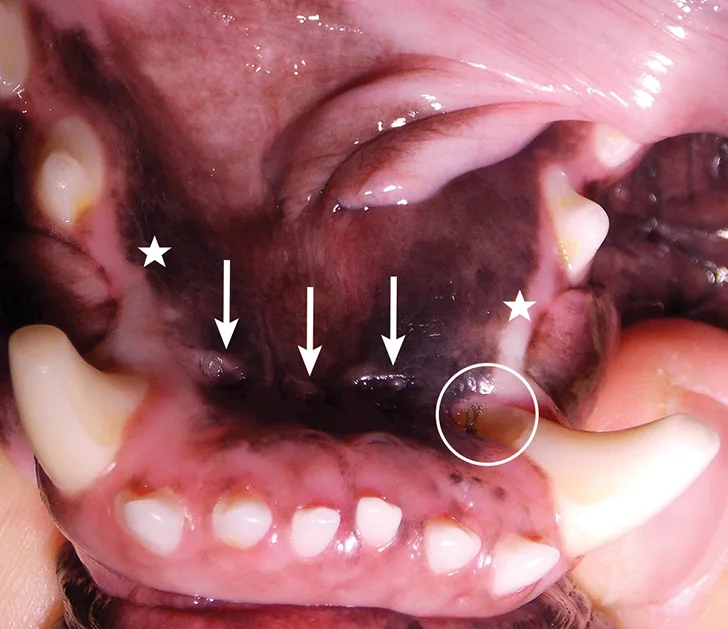

A thorough evaluation of the oral cavity (Figure 2) was performed with the patient under general anesthesia. Mandibular first premolars were not visible on clinical inspection. Mandibular mucosal trauma by the maxillary incisors and trauma to the left mandibular canine (304) tooth by the left second maxillary incisor (202) were observed. The patient also had oral masses present at the gingiva of the left rostral maxillary area covering the buccal surface of the premolar teeth (Figure 1).

Oral examination revealed nonvisible mandibular first premolars (stars), mandibular mucosal trauma by the maxillary incisors (arrows), and trauma to the left mandibular canine tooth (304) by the left second maxillary incisor (202; circle).